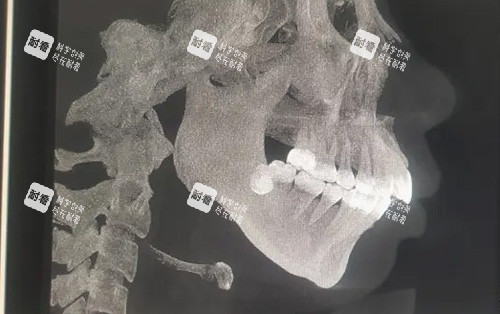

这些逆袭病例背后,是周会喜团队20年磨一剑的“硬核技术”。作为南方医学大学口腔颌面外科主管医师、广东省整形美容团队理事,他手里的“家伙事儿”可不止手术刀——CT影像+3D打印导板,能把颌骨截骨误差控制在0.1毫米内,“就像给骨头装了个GPS,避开神经血管,连‘歪嘴’都能精细复位!”

传统正颌手术要在脸上开外部切口,插引流管,术后肿得像“发面馒头”,改善期长达3个月。但周会喜团队用口内切口+超声电刀剥离组织,出血量不到传统手术的1/5,“术后不用插管,肿胀期缩短到1-2周,堪称‘午休式手术’!”更绝的是,他不仅修复咬合功能,还会根据五官比例设计颌骨形态——“月亮脸”求美者,他会增加下颌角宽度,告别“锥子脸违和感”;“大小脸”求美者,通过骨缝调整,让左右脸对称度堪比3D打印。